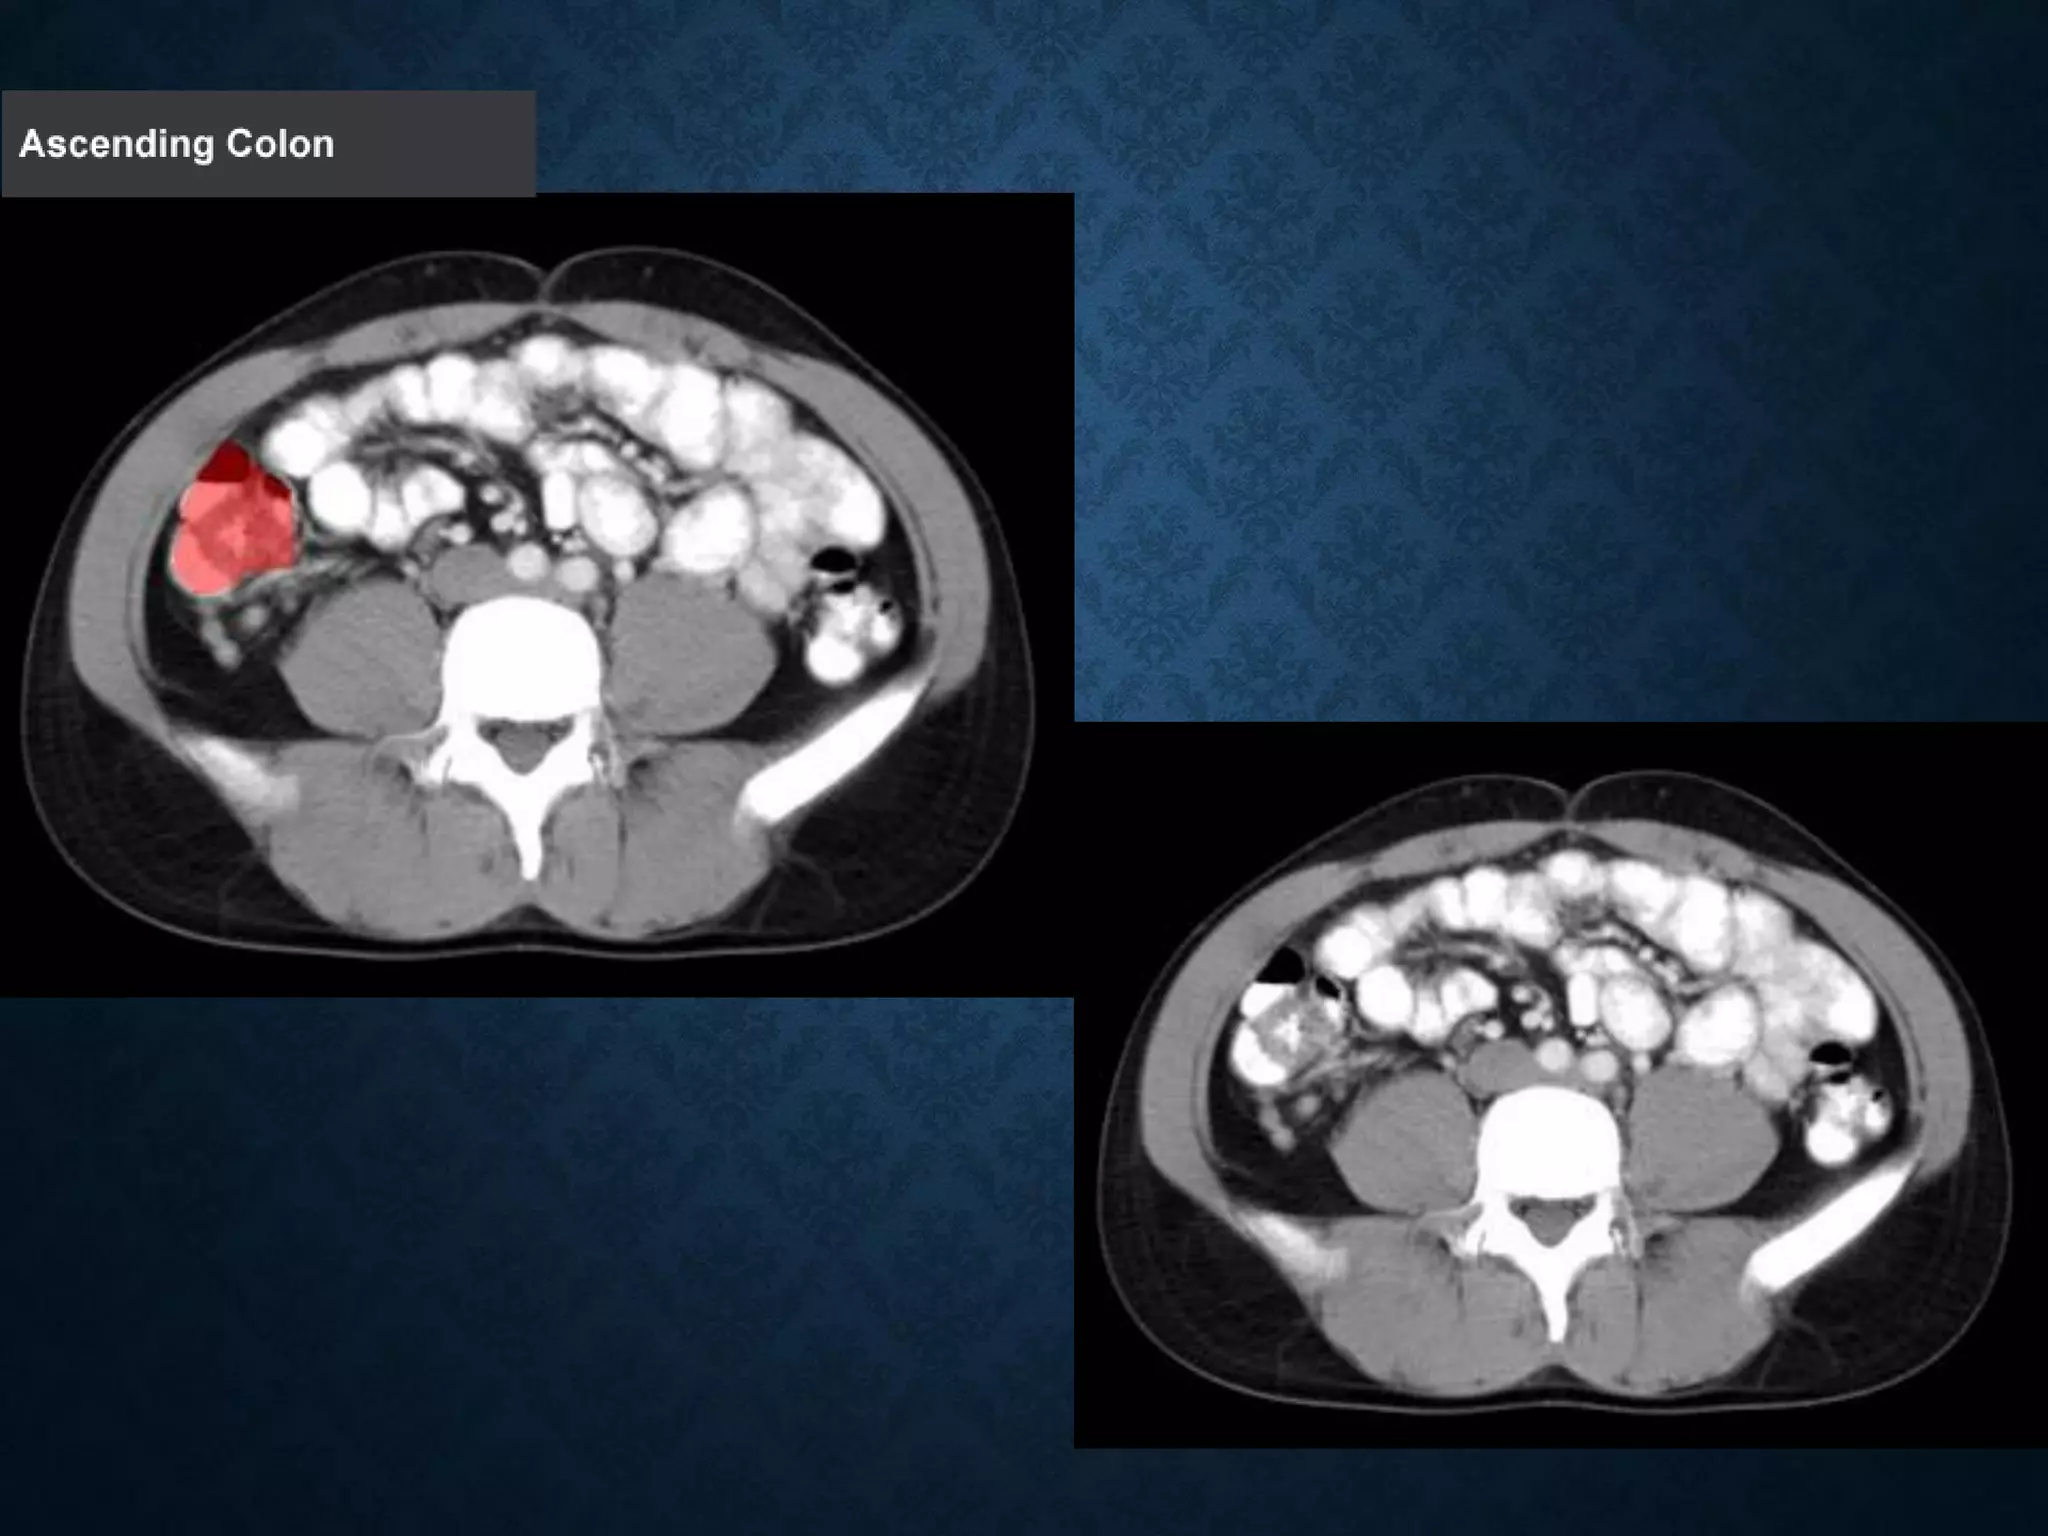

Identify the following structures in the body CT to the right. To view the location of the structure in the image click on

the label at the left and the structure will be indicated in the image. Abdominal CT scans typically begin just above

the diaphragm, so the first slice you see is of the lower chest.

Identify the followingstructures in the body CT to the right. To view the location of the structure in the image click on the label at the left and the structure will be indicated in the image. Abdominal CT scans typically begin just above the diaphragm, so the first slice you see is of the lower chest.